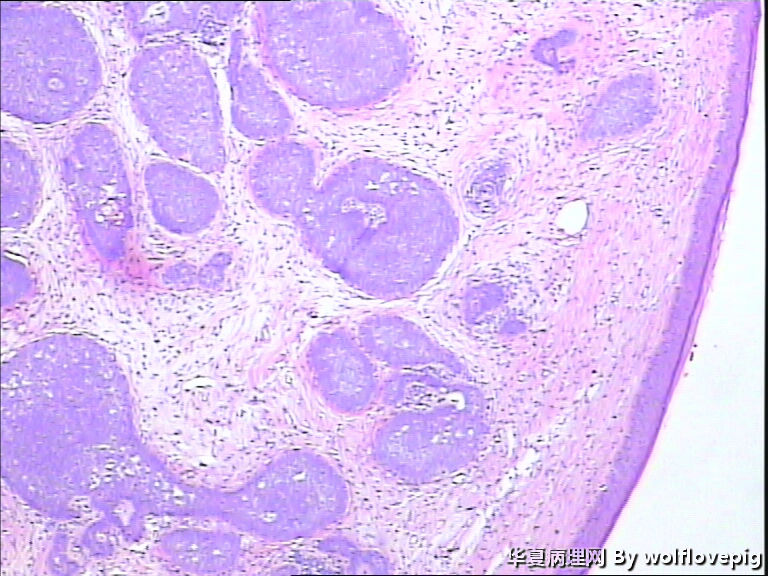

女,58y,右面部包块10年。灰白不整形带皮组织一块:2.3cm*1.5cm*0.3cm,切面有一灰白区域,质软,边界欠清。

诊断考虑毛母细胞瘤,或毛发上皮瘤。

基底细胞癌

毛母细胞瘤

毛发上皮瘤

没有基底样物质,没有收缩裂隙,细胞异型不大,无明确核分裂像,考虑:附属器肿瘤,有点像汗腺来源的,如真皮导管瘤或螺旋瘤。请老师指点。

栅栏状外周结构,疏松的间质,基底细胞癌

与表皮无关,表皮无破溃,无收缩间隙-------不支持BCC  有角囊肿 促纤维增生-----支持毛发上皮瘤